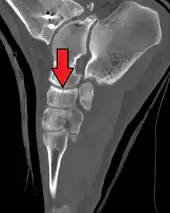

Fracture of the navicular bone

The human navicular is not a commonly broken bone but it breaks due to two reasons. The first mechanism is a stress fracture which happens commonly in athletes [7] and the other mechanism is a high energy trauma.

The navicular bone is a keystone of the foot: it is part of the coxa pedis and articulates with the talus, first, second and third cuneiform, cuboid and calcaneus. It plays an important role in the biomechanics of the foot, helping in inversion, eversion, and motion; it is a structural link between midfoot and forefoot and it is part of the longitudinal and transverse arch of the foot.